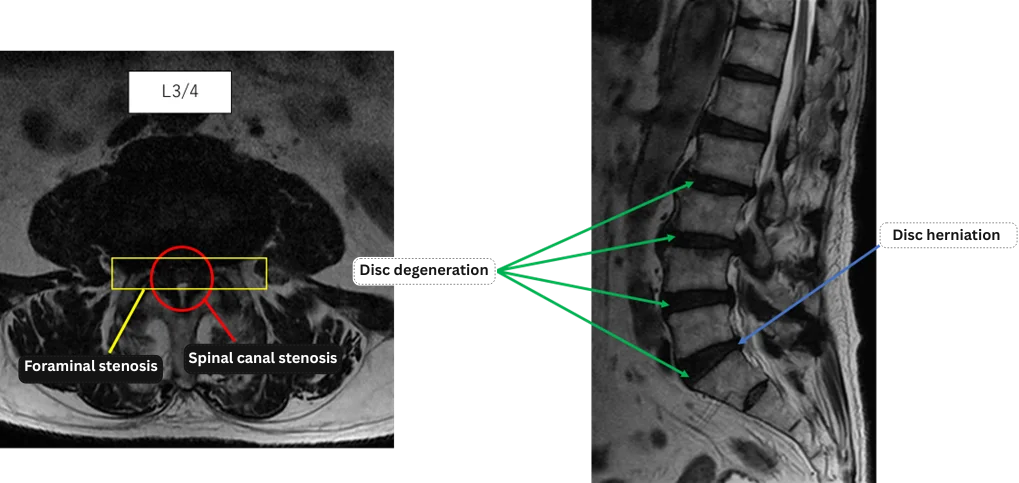

L1/2: Nothing unusual

L2/3: Disc degeneration, right foraminal stenosis

L3/4: Disc degeneration, spinal canal stenosis, bilateral foraminal stenosis

L4/5: Disc degeneration, left foraminal stenosis

L5/S: Disc degeneration, disc herniation, right foraminal stenosis

The above findings were also observed on the imaging.

Disc degeneration, disc bulging, and annular tear were observed at L2/3, L3/4, L4/5, and L5/S, which are considered highly likely to be the causes of the patient’s main symptoms.